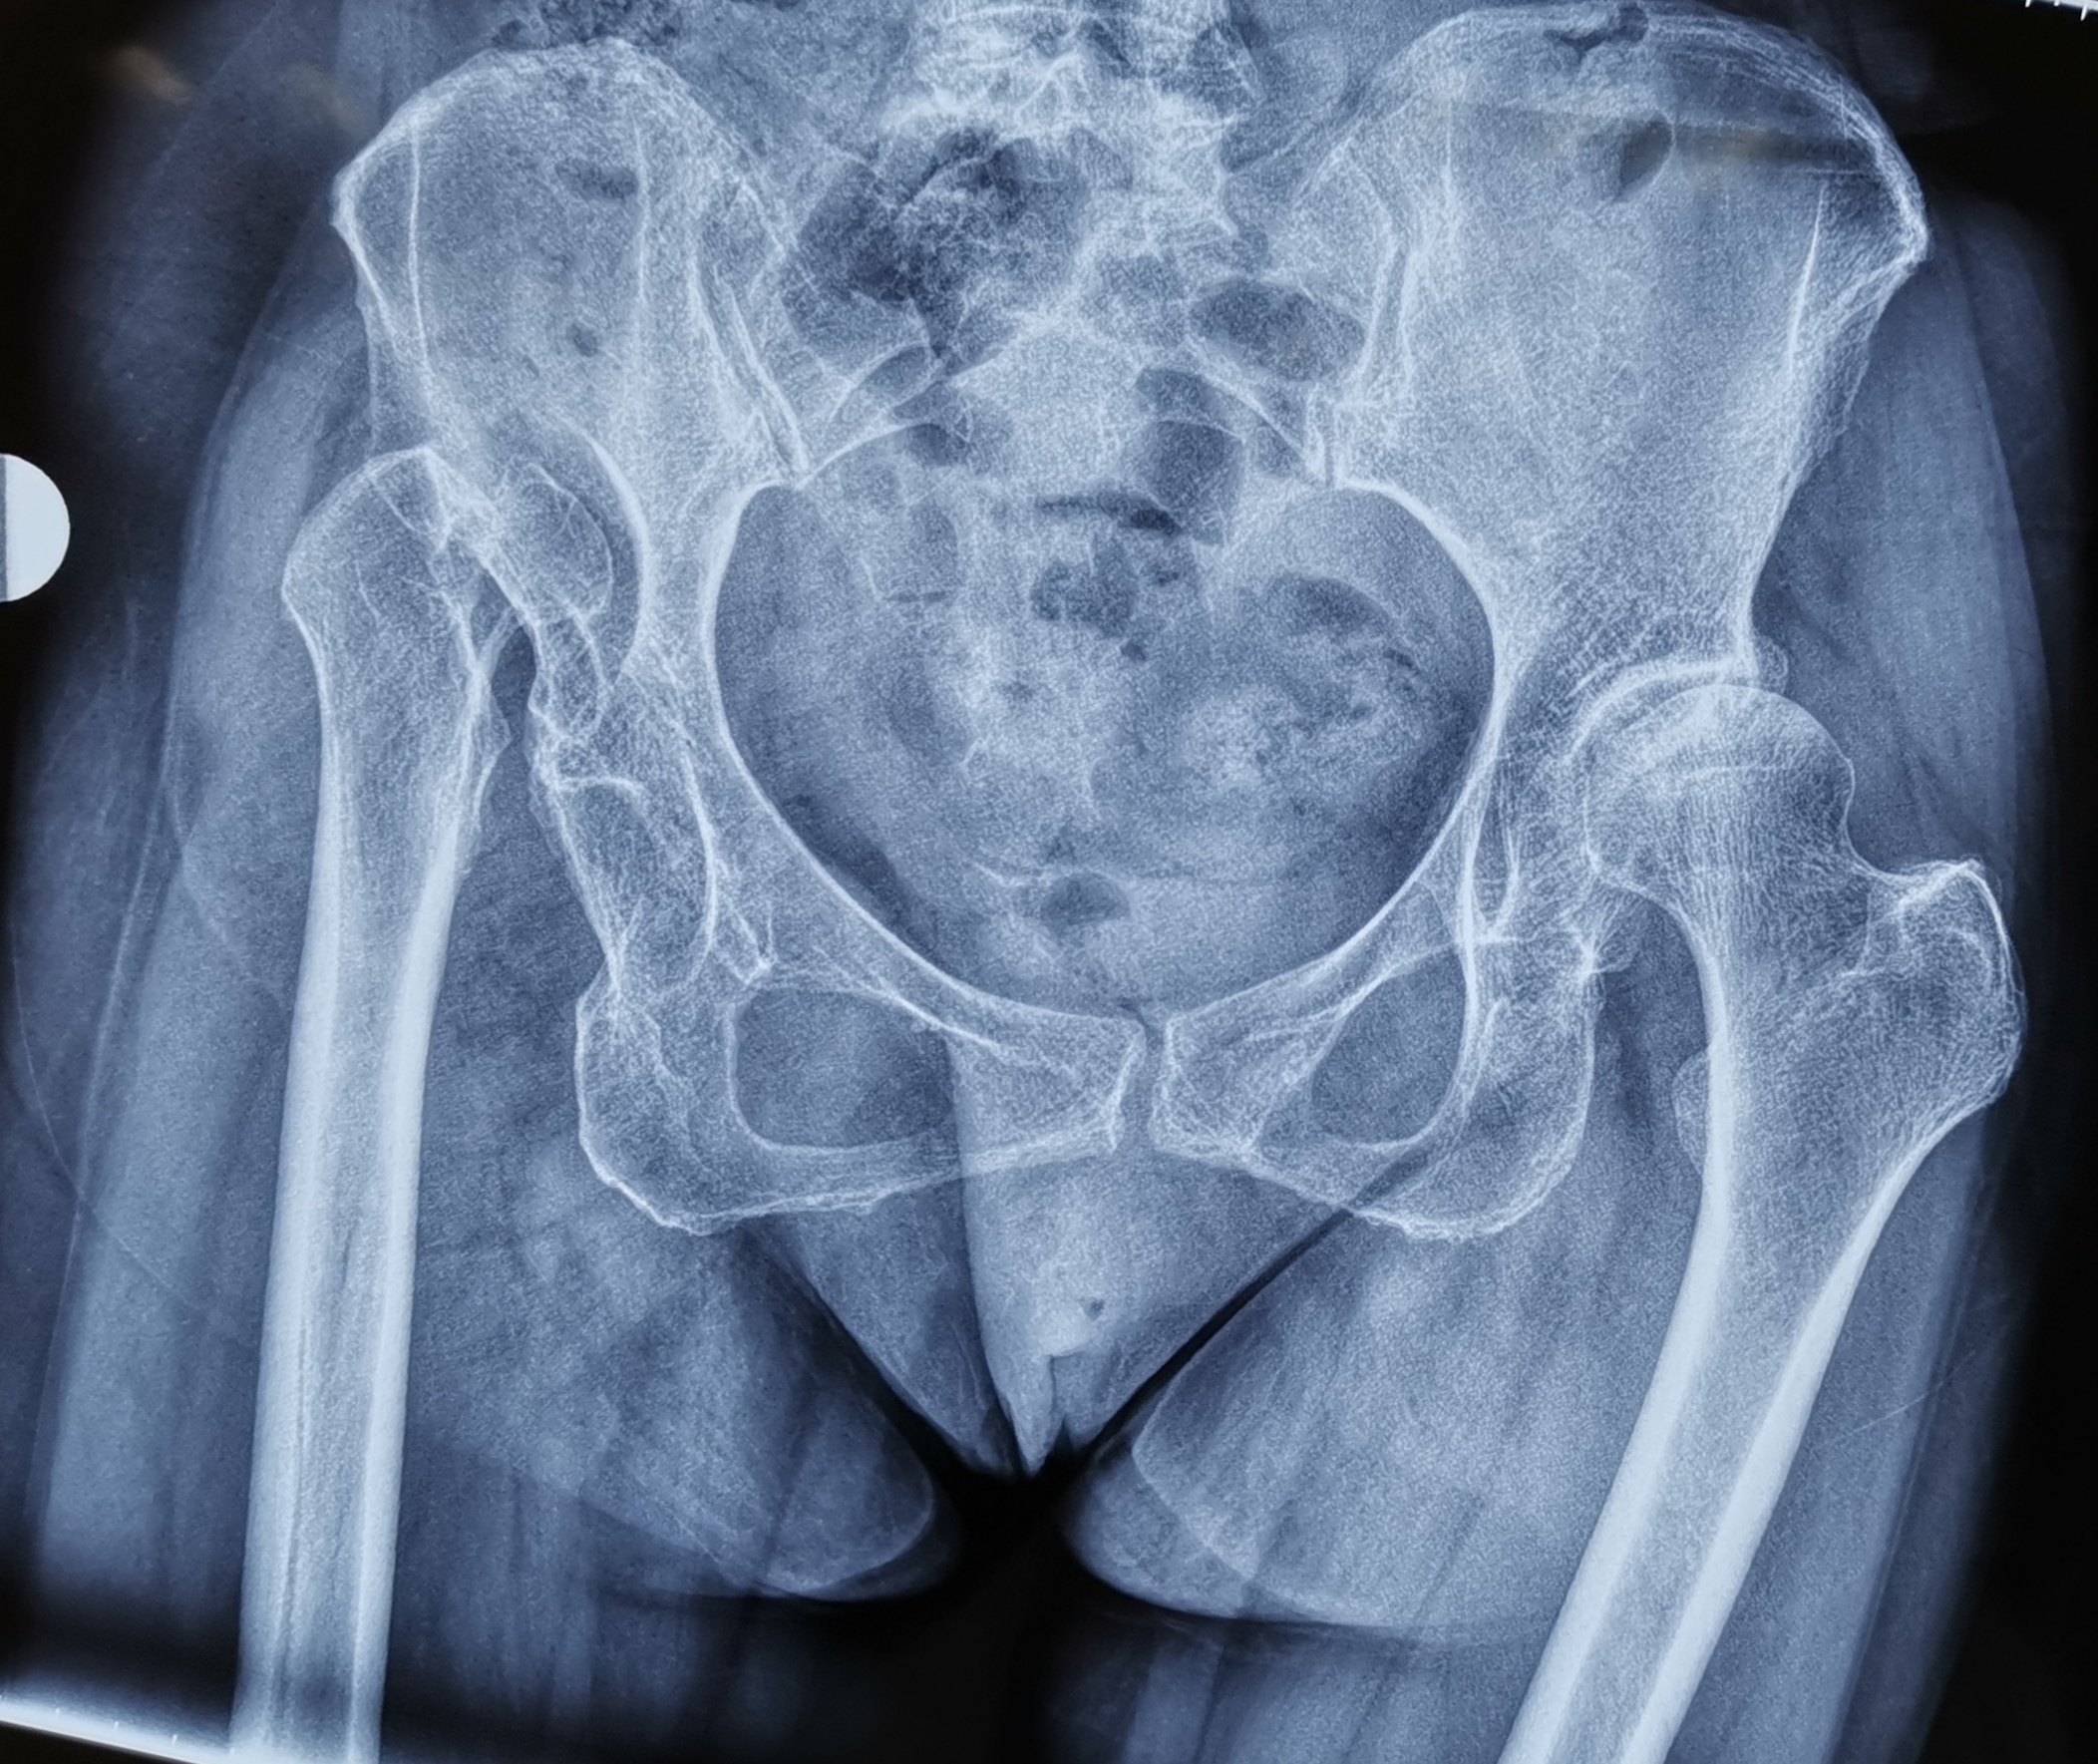

发育性髋关节发育不良是指由于髋臼发育缺陷造成髋臼对股骨头的覆盖不良,导致长期生物力学的异常而逐渐出现股骨头半脱位负重区软骨退变及股骨头局灶性囊性变,严重骨关节炎的一种疾病其主要病理改变表现为髋臼外上方和前方缺损,髋臼变浅,髋关节中心外移,致使髋臼对股骨头的包容与覆盖不足DDH可以。